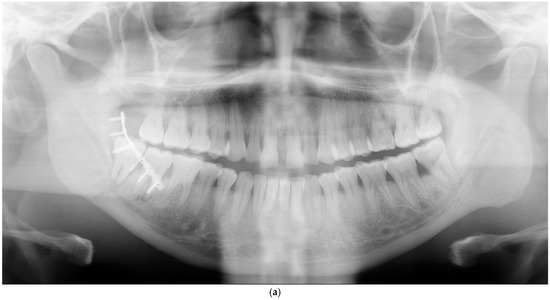

| Anterior part (symphysis/parasymphysis) | 5 | 2 | 3 inadequate reductions, 2 nonunions with infection | ||

| Angle | 3 | 2 | 1 inadequate reduction, 1 infection, 1 nonunion with infection | ||

| Body | 3 | 0 | 3 inadequate reductions | ||

| Condyle | 3 | 1 | 2 inadequate reductions, 1 broken plate | ||